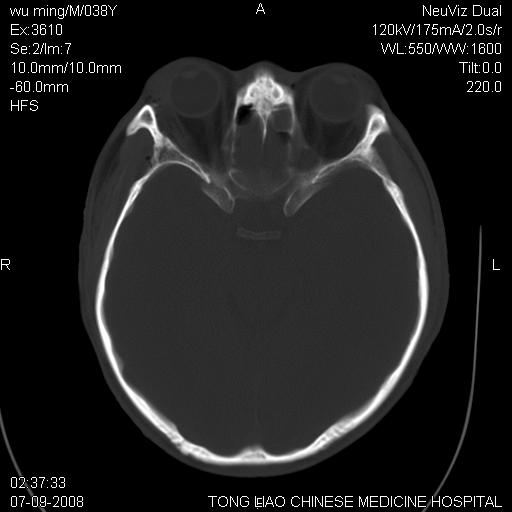

颅底多发骨折.上颌骨多发骨折

右侧眼眶,上颌骨,鼻骨、上颌窦等很多

1)颅底骨及颌面骨多发性骨折。2)副鼻窦及双侧鼻腔积血。

多发性颅骨骨折

颅底、上颌骨,双侧颧骨多发骨折。死因或许与此无关,是否有腹部脏器损伤有关